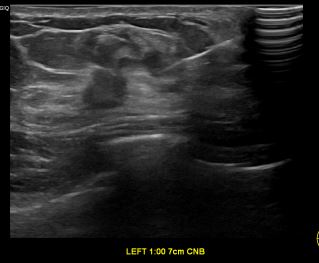

상기환자는 외부건강검진이상소견 정밀검사위해 내원하신 40대 후반

여성분으로 의심스러운 좌측유방혹 조직검사 시행해 유방암으로 진단되었습니다